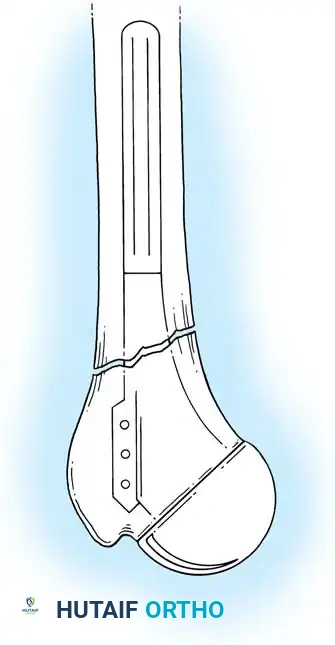

5. Humeral Preparation and Implantation

Broach the humeral canal sequentially. Assess the trial components for stability, ensuring 50% posterior translation on the "drawer test" and no superior escape. Implant the final prosthesis (press-fit or cemented based on bone quality).

3. Canal Preparation and Implantation

The humeral and ulnar canals are sequentially broached.

- A cement restrictor is placed in both canals.

- Antibiotic-loaded polymethylmethacrylate (PMMA) bone cement is injected in a retrograde fashion.

- The components are inserted, and the articulation is linked using the manufacturer-specific locking pin mechanism.